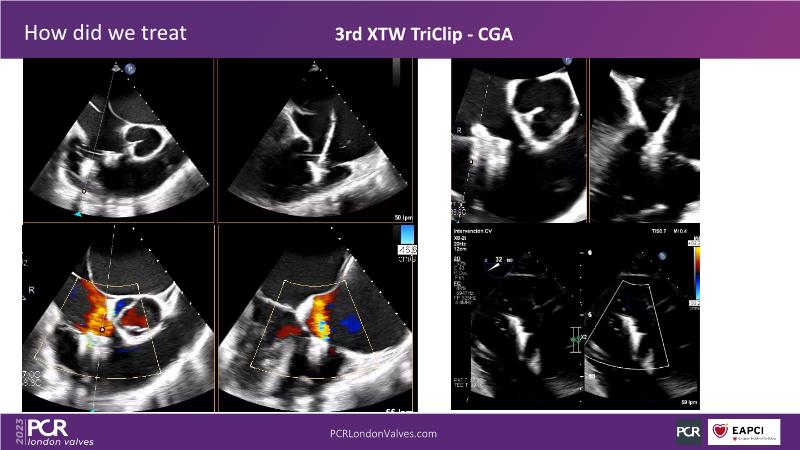

This session offers an opportunity to engage in a real case discussion led by an advanced Heart Team. Participate in discussions on controversial decision-making scenarios and stay informed about the latest clinical evidence related to MitraClip, Tendyne, and TriClip therapies.